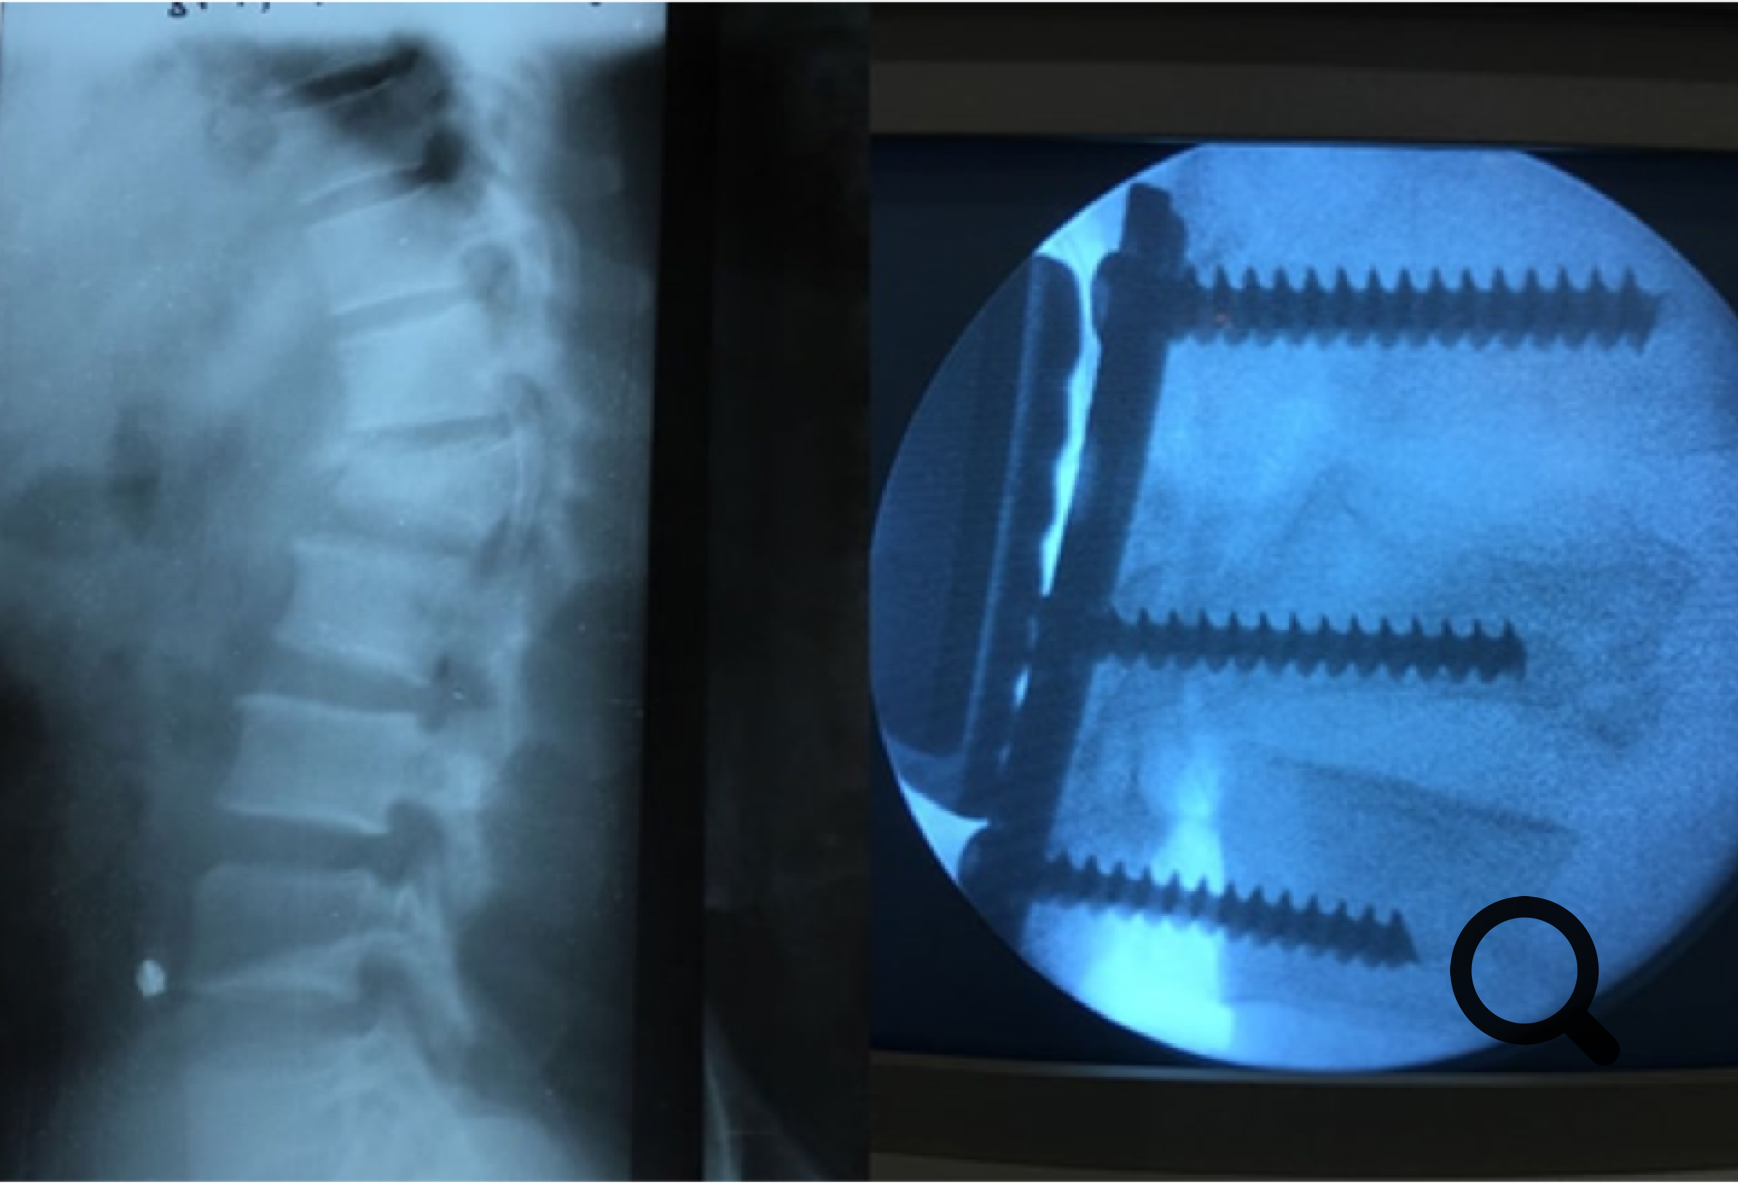

Venimos anunciando nuestra intención de iniciar la cirugía de la columna vertebral en 2018.

La ocasión se presentó con un paciente que tenía una grave fractura vertebral con una parálisis en miembro inferior. El Dr. Areta tuvo el coraje de operarle con los materiales de los que disponemos (actualmente no específicos para la cirugía de raquis) con un fantástico resultado y con una progresiva recuperación de la movilidad y fuerza muscular en su pierna paralizada.